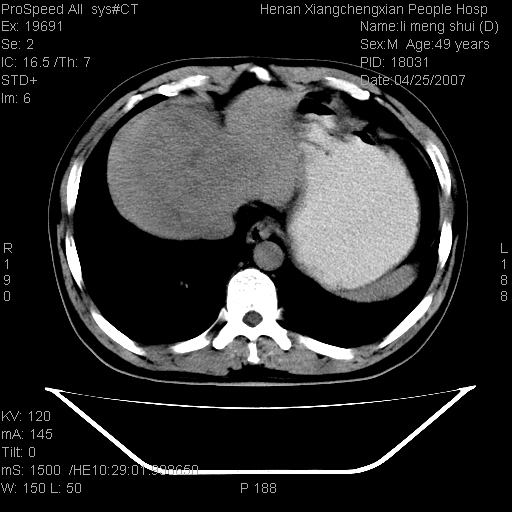

| 患者,男,49岁, 腹疼伴恶心\\呕吐20天,20天前无明显诱因出现右上腹部疼痛,钝疼,无放射,伴恶心\\呕吐,不伴发热.患者不愿增强. b超:肝脏右叶实性占位. ct:肝脏右叶可见一巨块状圆形低密度影,大小约93mm*84mm,其内可见点状高密度影,胆囊、胰腺、脾脏大小、形态及密度未见异常,腹膜后间隙未见肿大淋巴结影。 印象:肝脏右叶巨大肿块,性质待定,建议增强并穿刺活检进一步确诊。 ct平扫: ![]() ![]() ![]() ![]() ![]() ![]() ![]() ![]() ![]() ![]() ![]() ![]() ![]() ![]() ![]() ![]() ![]() 肝脏右叶肿块ct引导下穿刺活检术 患者于16时05分仰卧于ct检查台上,首先行肝脏ct扫描确定进针位置、深度、角度。在局麻下行ct引导下肝脏右叶肿块穿刺活检术。常规消毒、铺巾、局麻。在ct引导下使活检针经右侧腋中线、第9肋间隙垂直胸壁进针90mm,针头进入病变预定位置。在病变预定位置多点、多方向抽取小米样病变组织多块,涂片五张送病理检查。术后穿刺点局部无出血,未出现腹腔积液等并发症。术中及术后患者生命体征稳定,手术于17时10分成功完成。患者安返病房。 穿刺片 ![]() ![]() ![]() ![]() ![]() ![]() ![]() ![]() ![]() ![]() ![]() ![]() ![]() ![]() ![]() ![]() 病理结果肝细胞癌 ![]() 原贴地址:http://www.radinet.com.cn/forum_view.asp?forum_id=4&view_id=24130 ok |